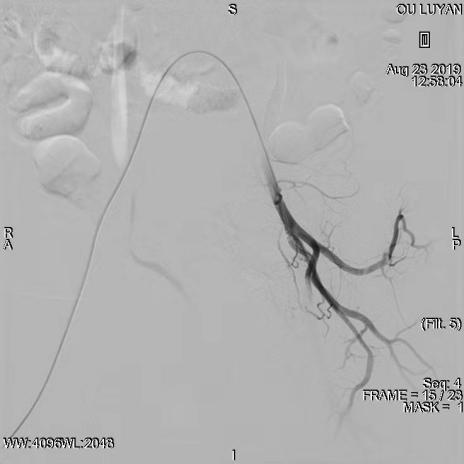

综合评估后考虑患者为Ⅱ型子宫切口妊娠,与患者及家属沟通后决定选择药物杀胚同时行双侧子宫动脉栓塞术。DSA显示双侧子宫动脉增粗、迂曲,均注入150-560um明胶海绵颗粒,造影显示栓塞满意。血β一HCG下降后在宫腔镜、B超引导下清除妊娠病灶,积极终妊。8月27日,手术过程进行顺利,未输血,患者于9月1日出院,后期继续加强康复治疗,预防远期并发症宫腔粘连发生。

右侧子宫动脉稍增粗、迂曲

栓塞术后右侧子宫动脉未见显影